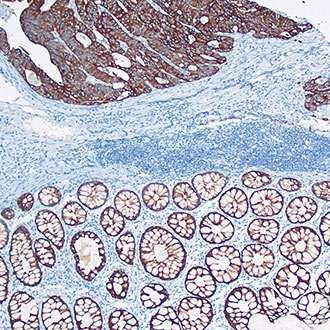

IHC

免疫组织化学(IHC)